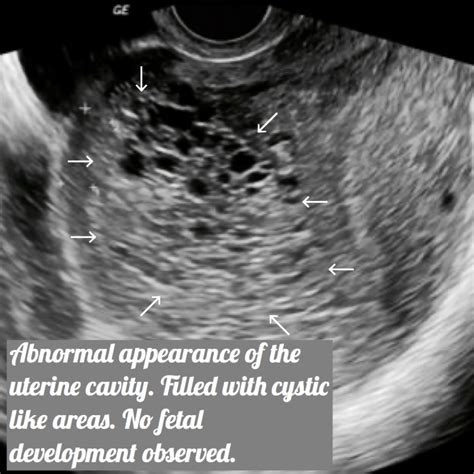

During the scan, a sonographer or radiologist uses high-frequency sound waves to create images of the uterine cavity. In a healthy pregnancy, the ultrasound will show a clear gestational sac with a developing fetus. In contrast, the imaging of a molar pregnancy displays distinct patterns that deviate from normal development.

Radiologists look for specific visual markers to identify this condition. The most classic description of a molar pregnancy ultrasound image is often called the "snowstorm" appearance. This occurs because the abnormal placental tissue creates multiple echo-producing interfaces, making the interior of the uterus look like a blizzard on the screen.

• Absence of Fetal Parts: In a complete mole, there is an absolute lack of fetal tissue.

• Cystic Spaces: Large, fluid-filled cysts are often visible within the mass.